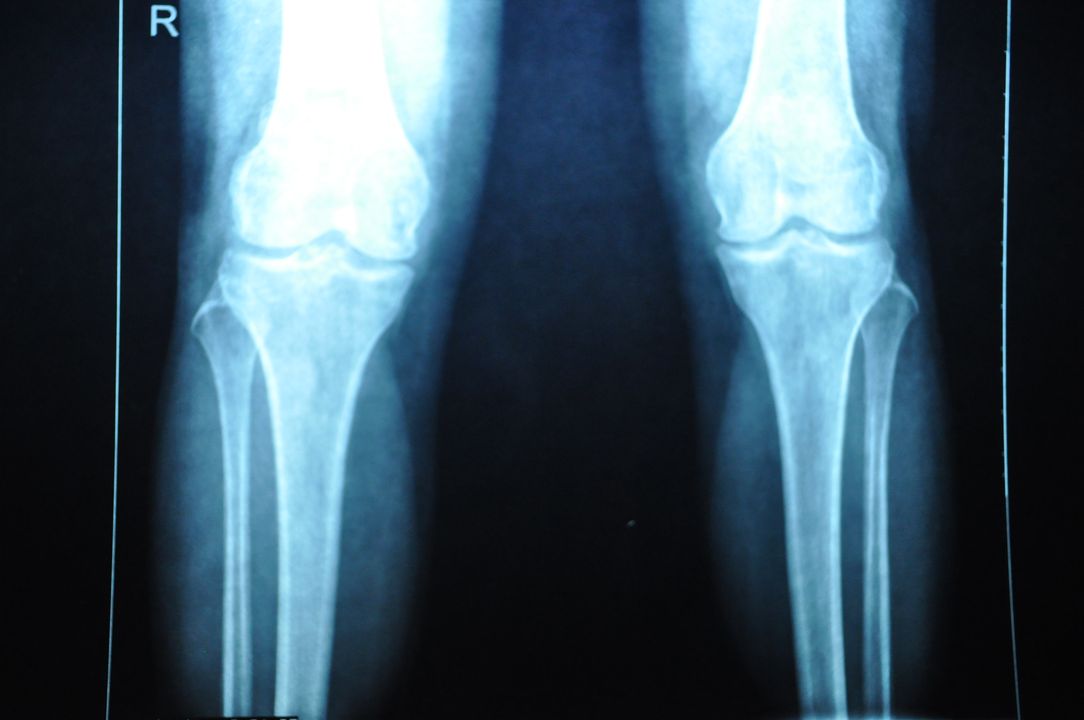

退行性膝关节炎辅助检查

X片检查